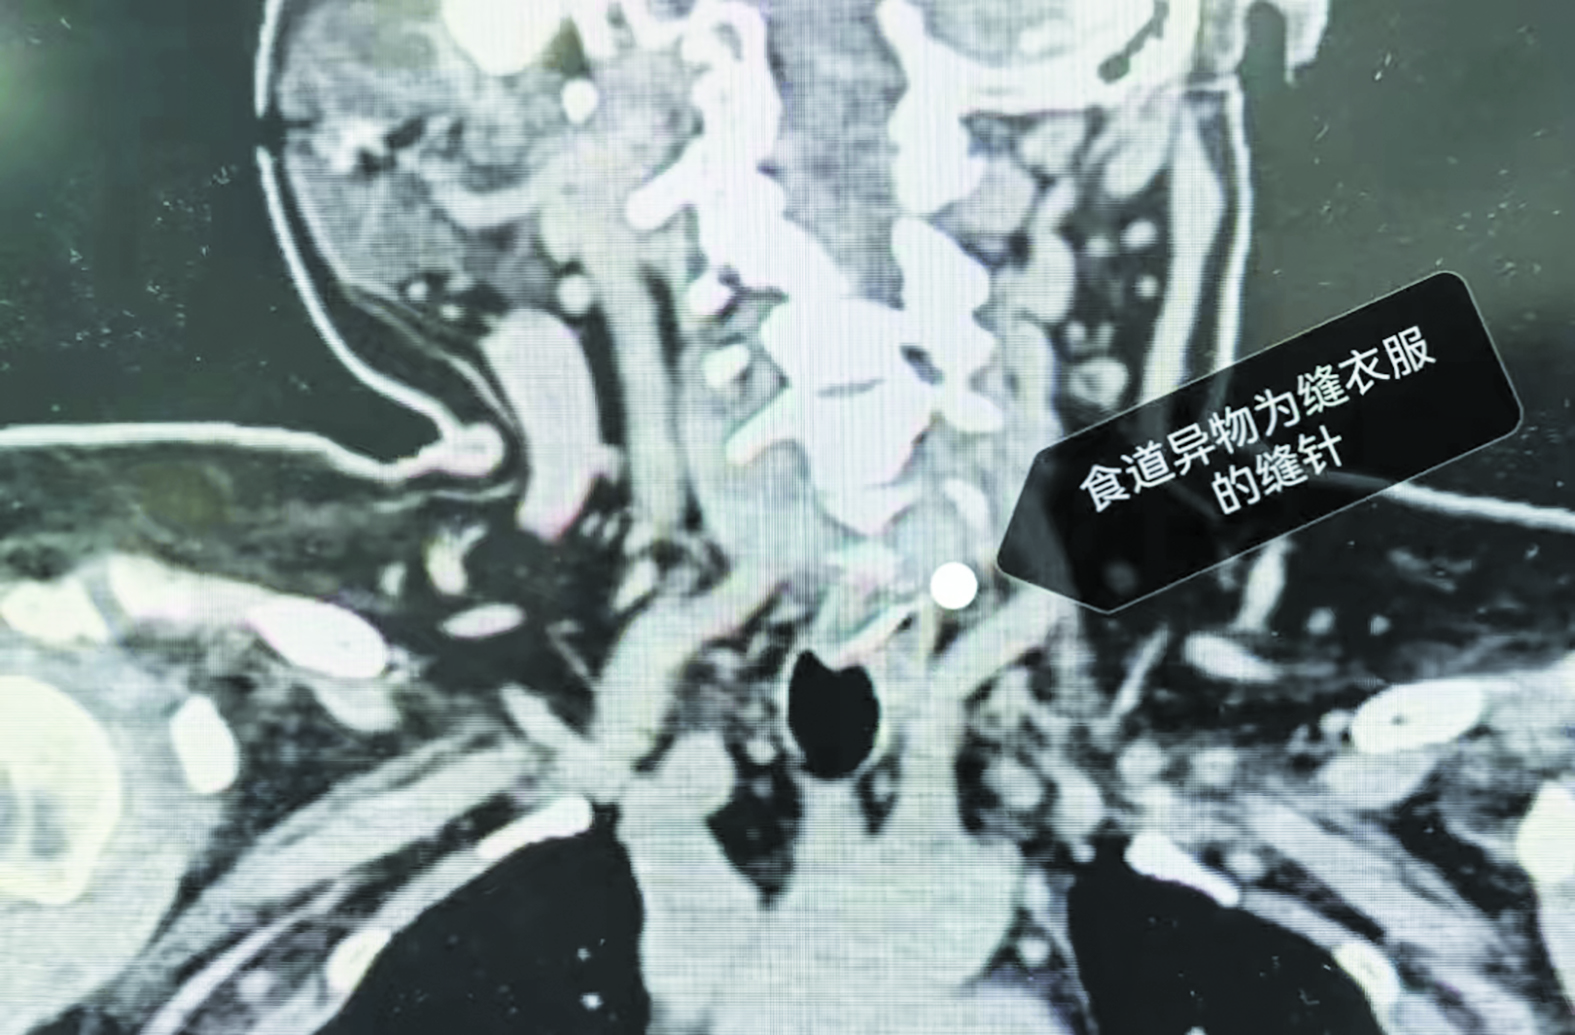

• 拍片显示,缝衣针卡在女子食道。视频截图

本报讯(株洲晚报融媒体记者/李毅哲) 近日,石峰区一名56岁的女子不慎将缝衣针吞进了食道,经紧急手术后取出。

据女子说,当时家里人择菜时,不慎把缝衣针混入菜中,然后一把炒了。她吃饭时也没注意,在玩手机,针便卡在了食道。

湖南省直中医医院耳鼻咽喉头颈外科主任龚兴宏带领手术团队为女子进行了紧急手术,成功将针取出。